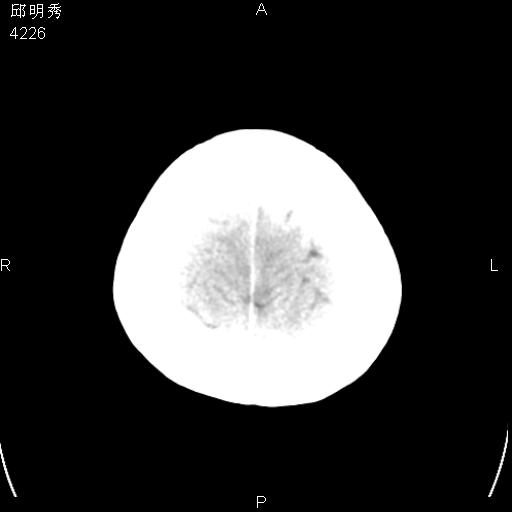

40f头晕十多天,右上肢麻木一天

脑白质变性或ms

脑白质脱髓鞘改变。

脑白质病;建议行mri检查。